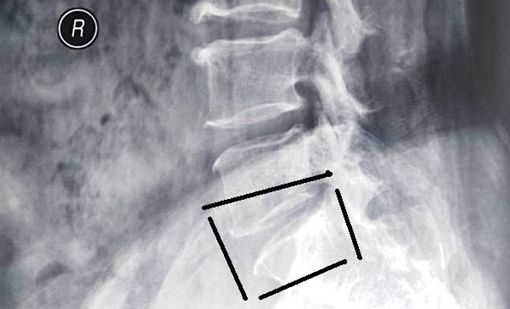

头痛 恶心呕吐,椎动脉型颈椎病的主要症状